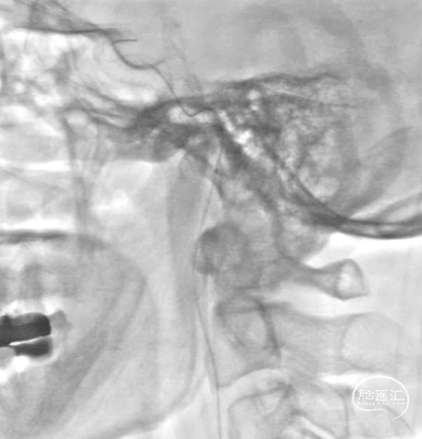

造影结果:右侧颈内动脉闭塞,经由颈外动脉-眼动脉反流至C6,可见右侧颈内动脉C2至右侧大脑中动脉M1显影(图1.a);右侧椎动脉V1重度狭窄(图1.c);左侧颈动脉造影可见前交通开放,右侧大脑中动脉浅淡显影(图1.b);左侧椎动脉造影显影正常(图1.d)。

图1. a组:RC造影;b组:RV造影;c组:LC造影;d组:LV造影

使用0.014" 300cm 微导丝尝试通过闭塞段困难,更换V-18微导丝带多功能导管至颈总动脉末端,再次尝试通过闭塞段缓慢通行至C1远段。

V-18微导丝通过RC起始段

V-18微导丝探路C1

更换0.014" 300cm 微导丝带2.0*20mm Emerge球囊继续向前探索通行至C1远段,造影确认导丝位置及血管位置。

造影确认导丝位置

撤出球囊导管及多功能导管,沿0.014" 300cm 微导丝将Rebar-18微导管输送至微导丝头端,撤出微导丝,沿微导管将0.014" 205cm 微导丝送入,尝试使用微导丝带微导管走远,顺利到达颈内动脉末端,撤出0.014" 205cm 微导丝,沿微导管冒烟提示真腔。

沿Rebar-18微导管将5.0*35mm Syphonet®取栓支架送至C7,撤出微导管释放Syphonet®取栓支架。